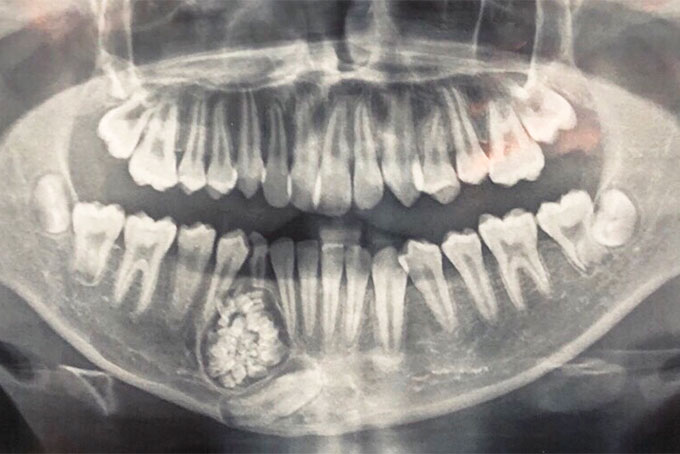

Cách đây không lâu, BN Trần Cao C. (54 tuổi, thị xã Ninh Hòa) thường có cảm giác tê bì ở tay, chân trái, thi thoảng khó vận động và hầu như không cầm nắm được đồ vật ở tay trái. Sau khi khám tại BVĐK tỉnh, các bác sĩ cho biết BN C. có khối u ở não với kích thước 2,3cm x 3,6cm. Giữa tháng 5-2019, BN C. quyết định phẫu thuật. Qua phẫu thuật, các bác sĩ Khoa Ngoại thần kinh của BV đã lấy ra khối u ở não cho BN. Sau phẫu thuật, sức khỏe của BN C. ổn định, các triệu chứng về vận động được cải thiện đáng kể.